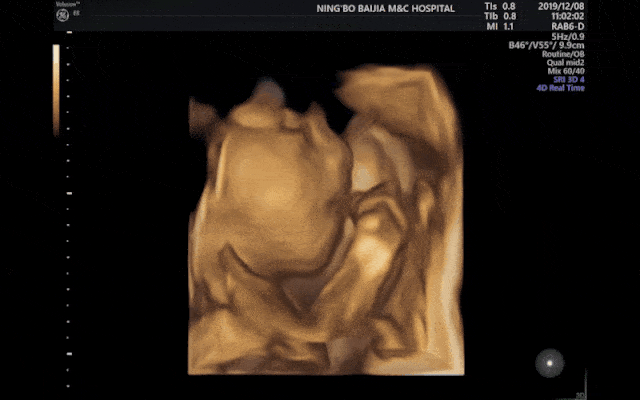

孕男宝生殖彩超图,男宝彩超图片男女

彩超单看胎儿性别,您学会了吗?|女宝宝|孕囊_网易订阅

四维彩超的最佳时间,很多孕妈都做早了

火遍小红书的四维彩超你还不知道吗?艾博尔医院科普_检查_超声_胎儿

原创孕检时符合这4种情况可能怀男宝的几率比较高